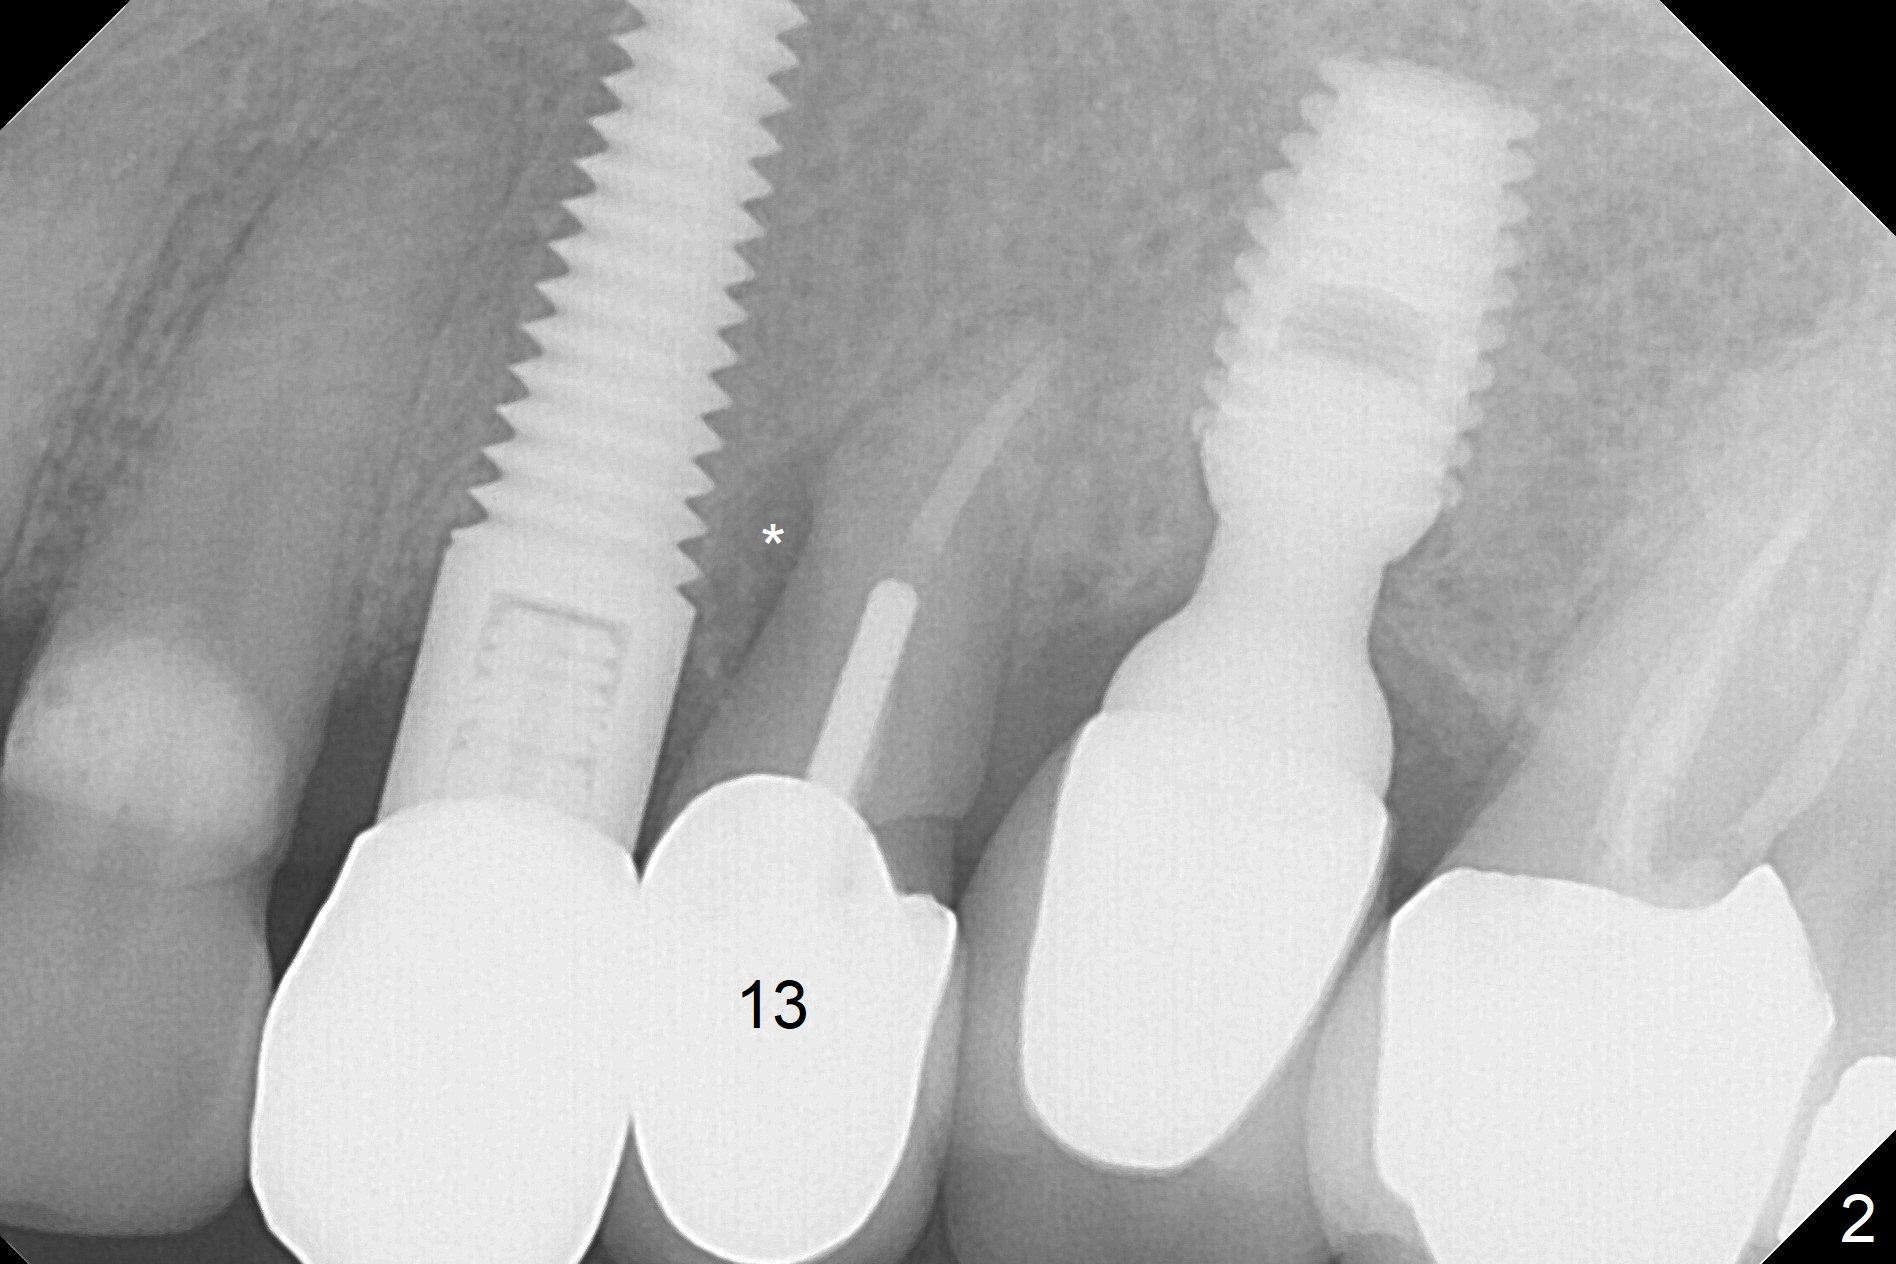

A 59-year-old woman has mild discomfort in the upper left quadrant, which is alleviated by salt water rinse. The buccal gingiva recedes at #13 with mesiobuccal swelling and deep pocket (Fig.1,3), corresponding to the mesial radiolucency (Fig.2 *). The tooth appears to have vertical fractured root, as related to the retention post. Since the root tip curves distal, the initial osteotomy (Fig.5 red) should be established in the mesioapical slope after extraction (black). Following initial entrance, the trajectory will be changed to the long axis of the space (Fig.6) with PA to be taken. Measure the depth of the buccal crest against the buccal, proximal and palatal gingival margins. Place an implant, the same as #12 (4.5x20 mm) unless the mesiobuccal defect is extremely large (UF).